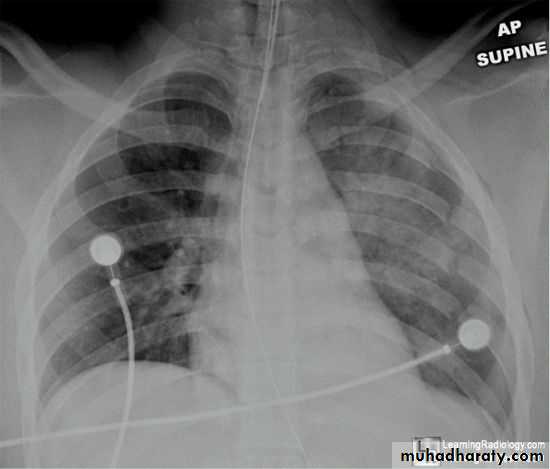

Patient with fever, rigor and dyspnea